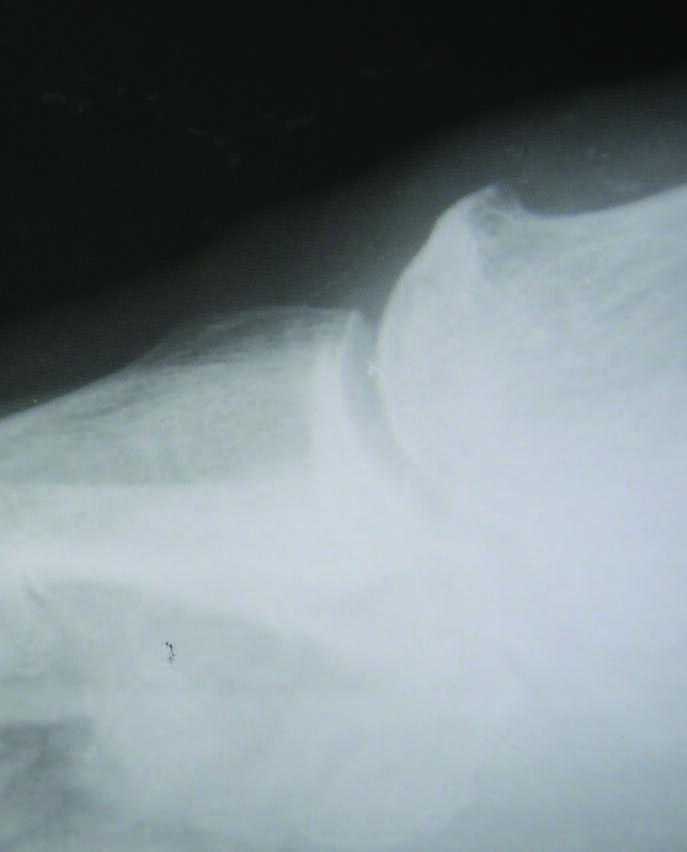

Stage 2. In stage 2, there is more dramatic loss in dorsiflexion at the first MPJ with only 10 to 30 degrees of dorsiflexion remaining, which can make ambulation difficult as well as painful.17 Radiographically, a more extensive dorsal osteophyte will be seen than in stage 1, with further decrease in the joint space. This stage now represents a structural hallux limitus.

Stage 3. In stage 3, the patient has lost nearly all motion in the first MPJ, now with less than 10 degrees of dorsiflexion remaining, and movement of the joint to the end range of motion causes the patient significant pain.17 Radiographically, there will be significant joint space narrowing, joint destruction, and with possible sesamoid change. This stage by definition constitutes a hallux rigidus.